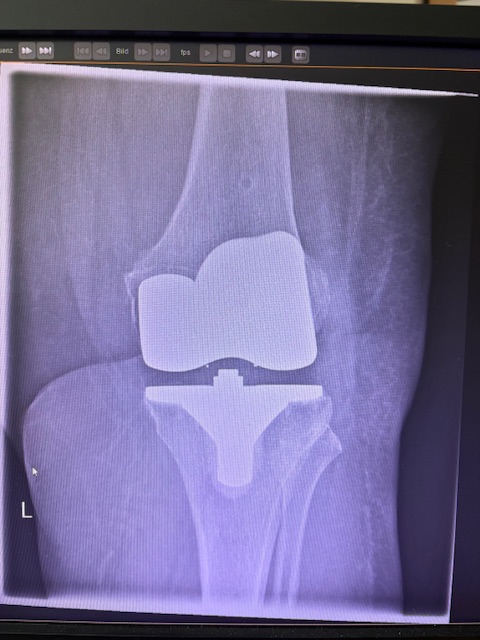

Τα εμφυτεύματα που χρησιμοποιήθηκαν στο γόνατο της ασθενούς είναι της Aesculap: E-Motion Pro, μηριαίο μέγεθος 4, κνημιαίο μέγεθος 4, με ενθέμα (inlay) 10mm.

Η επέμβαση ολοκληρώθηκε χωρίς επιπλοκές, με ελάχιστη απώλεια αίματος και ταχεία κινητοποίηση της ασθενούς.